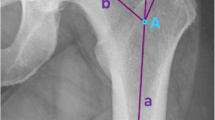

Measuring the lesser trochanteric version

The lesser trochanteric version is the angle between the epicondylar axis of the knee joint and the transverse axis of the lesser trochanter (lesser trochanteric axis). Measurements of the posterior condylar axis were used to validate the epicondylar axis [9]. The lesser trochanter cannot be visualised as a whole in the transverse plane because of its posterior and cephalad orientation; therefore, the lesser trochanter axis was defined as the line passing through the centroid of the base of the lesser trochanter on the slice that showed the largest width of the lesser trochanter and the centroid at the tip of the lesser trochanter (Fig. 1).

Measuring the native collo-trochanteric angle

The collo-femoral version with respect to the lesser trochanter (native collo-trochanteric angle) was defined as the angle between the collo-femoral axis and the lesser trochanter axis. The slice at the level of the most proximal portion of the inferior neck that had no head portion was selected for measuring the collo-femoral axis. This level provides the most accurate estimate of the neck axis with the single slice method [10] and is consistent with the level of the collum osteotomy in THA. At this level, the collo-femoral axis was defined as the line passing through the midpoints at both the medial and lateral edges of the central portion of the neck (Fig. 2).